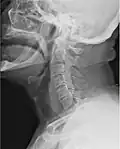

Beeldvormend medisch onderzoek van de menselijke keel waarbij gebruik wordt gemaakt van röntgenstraling. -